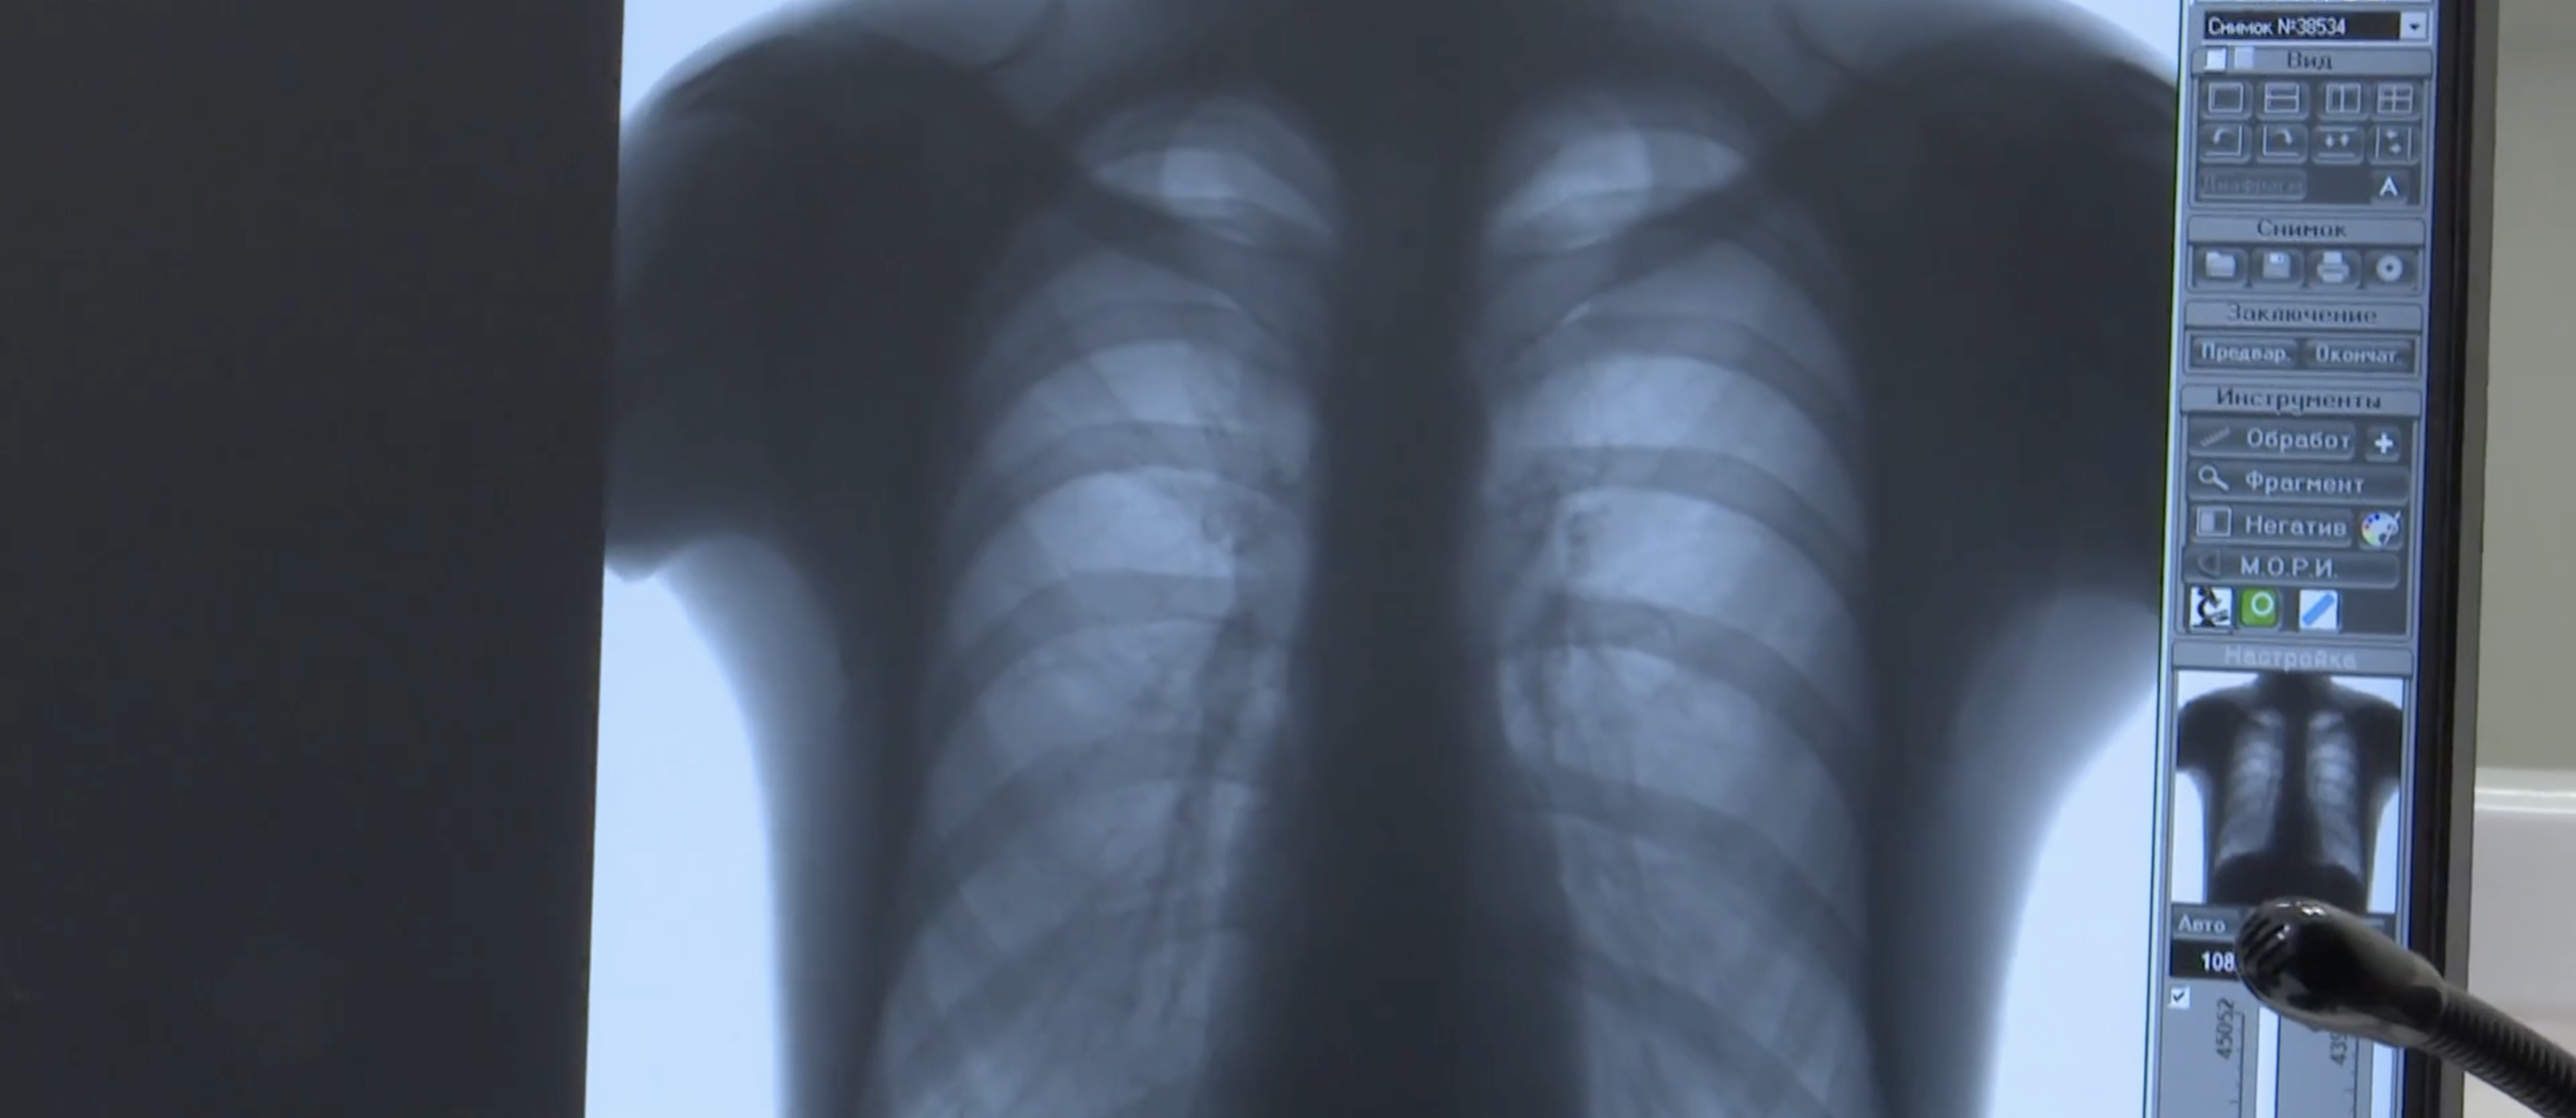

Согласно статистике, в Саратовской области курят порядка 500 тысяч человек. С 8 по 14 декабря в регионе проводится неделя профилактики потребления никотиносодержащей продукции. В лечебных учреждениях можно пройти диагностику, сделав флюорографию или спирографию, в ходе которой измеряется объем и скорость потоков воздуха при дыхании.